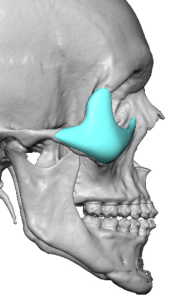

4. Lateral Extension (Zygomatic Transition)

- Blends into the malar eminence

- Prevents a central over-projection or “bulge”

- Ensures a smooth transition into the lateral orbit

- May extend onto the zygomatic arch when needed for continuity

Vector Correction Strategy

Rather than simply adding volume, the implant is designed to reposition skeletal support:

- Converts a negative vector to neutral or slightly positive

- Advances the infraorbital support structure to match or exceed globe projection

Fixation and Stability

- Screw fixation at the infraorbital rim and upper cheek

- Custom fit enhances positioning accuracy

- Orbital rim “saddling” improves stability and reproducibility